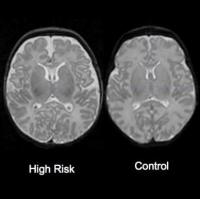

Известно, что шизофрению тяжело выявить до появления серьезных симптомов, связанных с маниями и галлюцинациями. Но к этому времени болезнь развивается до такой степени, что тяжело поддается лечению. Ученые из Университета Северной Каролины впервые выявили аномалии мозга, связанные с риском развития шизофрении у младенцев нескольких недель от роду. Таким образом, они смогут опознать детей, склонных к заболеванию, и принять соответствующие меры, считает Джон Х. Гилмор, профессор психиатрии. Они применяли ультразвук и МРТ, чтобы исследовать развитие мозга 26 младенцев, рожденных у матерей с шизофренией. Известно, что в таком случае риск болезни возникает у каждого десятого. Оказалось, что у мальчиков был больше объем мозга за счет боковых желудочков, заполненных жидкостью. Однако мозг девочек развивался одинаково, ведь известно, что шизофрения чаще появляется у мужчин. Результаты исследования не означают, что большой объем мозга обязательно указывает на шизофрению. Иногда врачи не обнаруживают у пациентов с этим диагнозом никаких изменений. Ученые собираются продолжить исследования, наблюдая за детьми в процессе развития моторных навыков и памяти. Источник: ScienceDaily